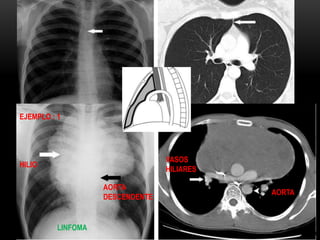

EJEMPLO : 1

AORTA

DESCENDENTE

HILIO

LINFOMA

VASOS

HILIARES

LA LINEA DEUNION ANTERIOR EJEMPLO : 1 AORTA DESCENDENTE HILIO LINFOMA VASOS HILIARES AORTA